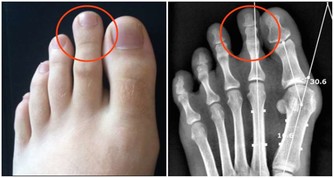

通過健康的生活方式,如運動、飲食和避免毒素,可以預防高達50%的癌症。建議大家經常鍛煉,即使每次只鍛煉很短的時間也好。養成少吃糖和重度加工食品,多吃水果和蔬菜的健康飲食習慣也很重要。

不是患了癌症從此就必須臥床的,運動幾乎具有普遍積極的效果,它是一種有益於身體多個系統的治療方法,可以永久改變腫瘤內的環境。當然,運動強度與時間要適量,別太勉強。